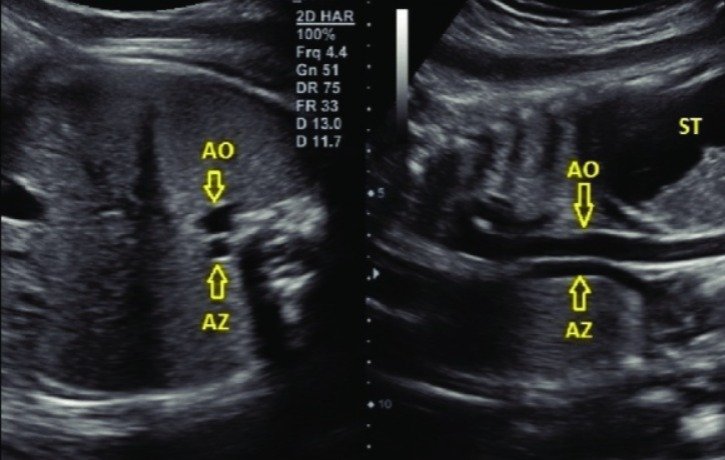

Double vessel (barrel ) sign in left atrial isomerism, heterotaxy

Double vessel sign: 2 vessels noted behind the heart in plane 0

transverse and sagittal scans of the fetal abdomen at 27 weeks of gestation. The dilated azygous vein (AZ) is located side-by-side and slightly posterior to the descending aorta (AO) along the spine